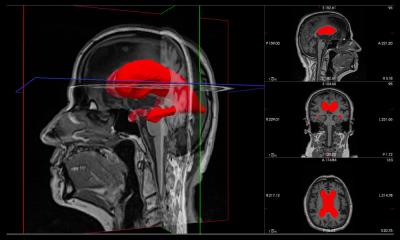

The researchers scanned the brains of over 70 study participants as they watched footage from the popular TV series. Half of the participants were familiar with the show’s famously complex lead characters and the other half had never seen the series. When lead characters appeared on screen, MRI scans showed that in neurotypical participants who were familiar with the characters, brain activity increased in regions of the brain associated with non visual knowledge about the characters, such as who they are and what we know about them.

Interestingly, connections between the visual brain and these non-visual regions were also increased in people who were familiar with Game of Thrones. However, these waves of activity were significantly reduced in the group of neurotypical participants who had never watched the series.

To determine whether these regions are important for face recognition, the researchers then repeated the study in people with prosopagnosia. As with the previous group, half had watched Game of Thrones and half had never seen the series. Consistent with their difficulty in recognising faces, the effect of familiarity was not found in the same regions of the brain found in neurotypical participants. The connections between the visual and non-visual regions were also reduced in face blindness.